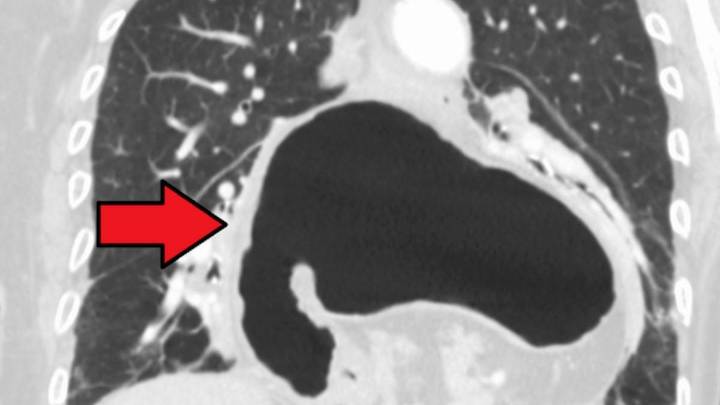

El hiato es un orificio situado en el diafragma que permite el paso del esófago hasta el estómago . Su función es importante ya que impide que el contenido del estómago refluya hasta el esófago. ¿Pero qué pasa cuando aparece una hernia en esta zona?

Pues al debilitarse o desplazarse esta zona parte del estómago se introduce o se hernia a través del hiato hacia el espacio torácico, provocando diversos síntomas o no. Porque hay pacientes que tienen hernia de hiato pero que no registran ninguna molestia , en cambio otros si sufren uno de los síntomas más habituales de esta patología: el reflujo .